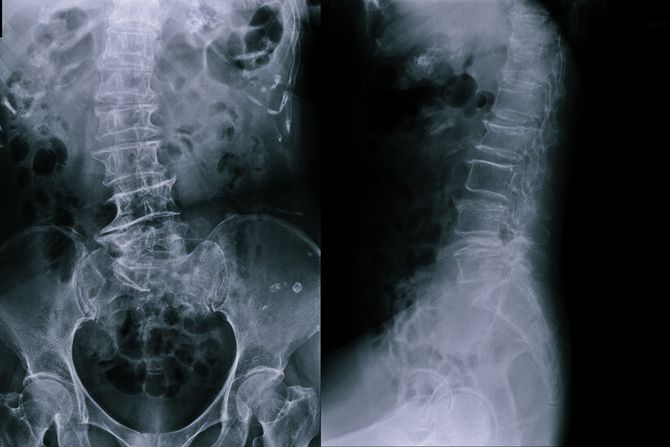

Li Hua je imao 18 godina kada je prvi put osetio bolove u kičmi. Pričao je s lekarima, obišao nekoliko bolnica, a onda je konstantovano da boluje od retkog poremećaja - ankilozirajućeg spondilitisa.

Serija od četiri visokorizične operacije dogodila se između 15. avgusta i 31. oktobra i uključivala je lomljenje kostiju i njihovo ponovno ispravljanje. Najduža je trajala 10 sati i 25 minuta.